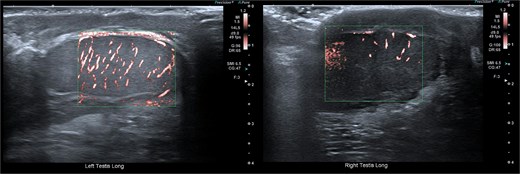

Closure was performed in layers, and local anaesthetic was infiltrated. The procedure was well tolerated. Follow-up at four weeks showed preserved testicular position with normal Doppler inflow and normal echotexture (Fig. 7).

Follow-up ultrasonographic image at 4 weeks post-operatively, demonstrating the left testis within the scrotum, with restored homogeneous echotexture and normal intratesticular vascularity on colour Doppler.